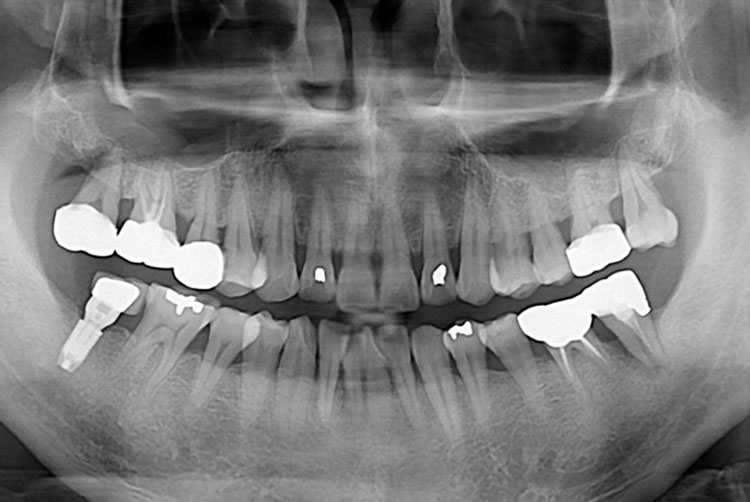

[임플란트] 임플란트

치료후 : 2017-08-01

세종치과는 많은 환자와 다양한 케이스를 바탕으로 항상 편안한 임플란트 수술을 제공하고자 노력하고,

오래동안 튼튼히 쓸 수 있는 임플란트 수술을 가장 큰 목표로 삼고 있습니다.